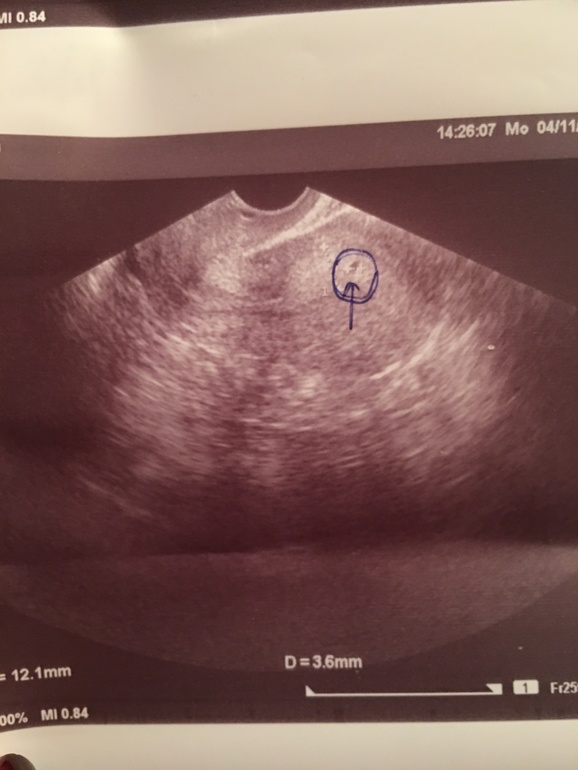

Задержка М и нет БЗадержка 3 день, тесты отрицательные. Сделала узи, говорит либо эндометрия(и скоро начнутся месячные) либо плодное яйцо(2.5мм) начало беременности. Может ли узист их перепутать? И как же их различить?

Диагноз: ранний срок беременности

Прилагаю фото

Тесты при таком плодном яйце были бы уже глубоко положительные.

Это складка эндометрия, он начинает отторгатся

Я поддержу общую тему: находили ПЯ предположительно, 1-2 мм, на узи как у вас выглядело, но и тесты/хгч были положительные. Без хгч это смысла не имеет, тк ещё много что может такой форм-фактор в матке иметь. Поэтому даже моя узистка моё микроскопическое ПЯ тогда не записала в заключение узи.

Размеры матки, толщина эндометрия, наличие и размеры жёлтого тела? Давайте уж все заключение с УЗИ.

На третий день задержки размеры эмбриона заведомо меньше разрешающей способности любого ультразвукового аппарата, так что это превращается в гадание на кофейной гуще

Думаю, что хороший узист точно не перепутает... Или аппарат узи настолько древний, что они не могут на нем определять. У меня плодное яйцо определили, когда оно было 2 мм. Но с плодным яйцом 2,5 мм, тесты не могут быть отрицательными.